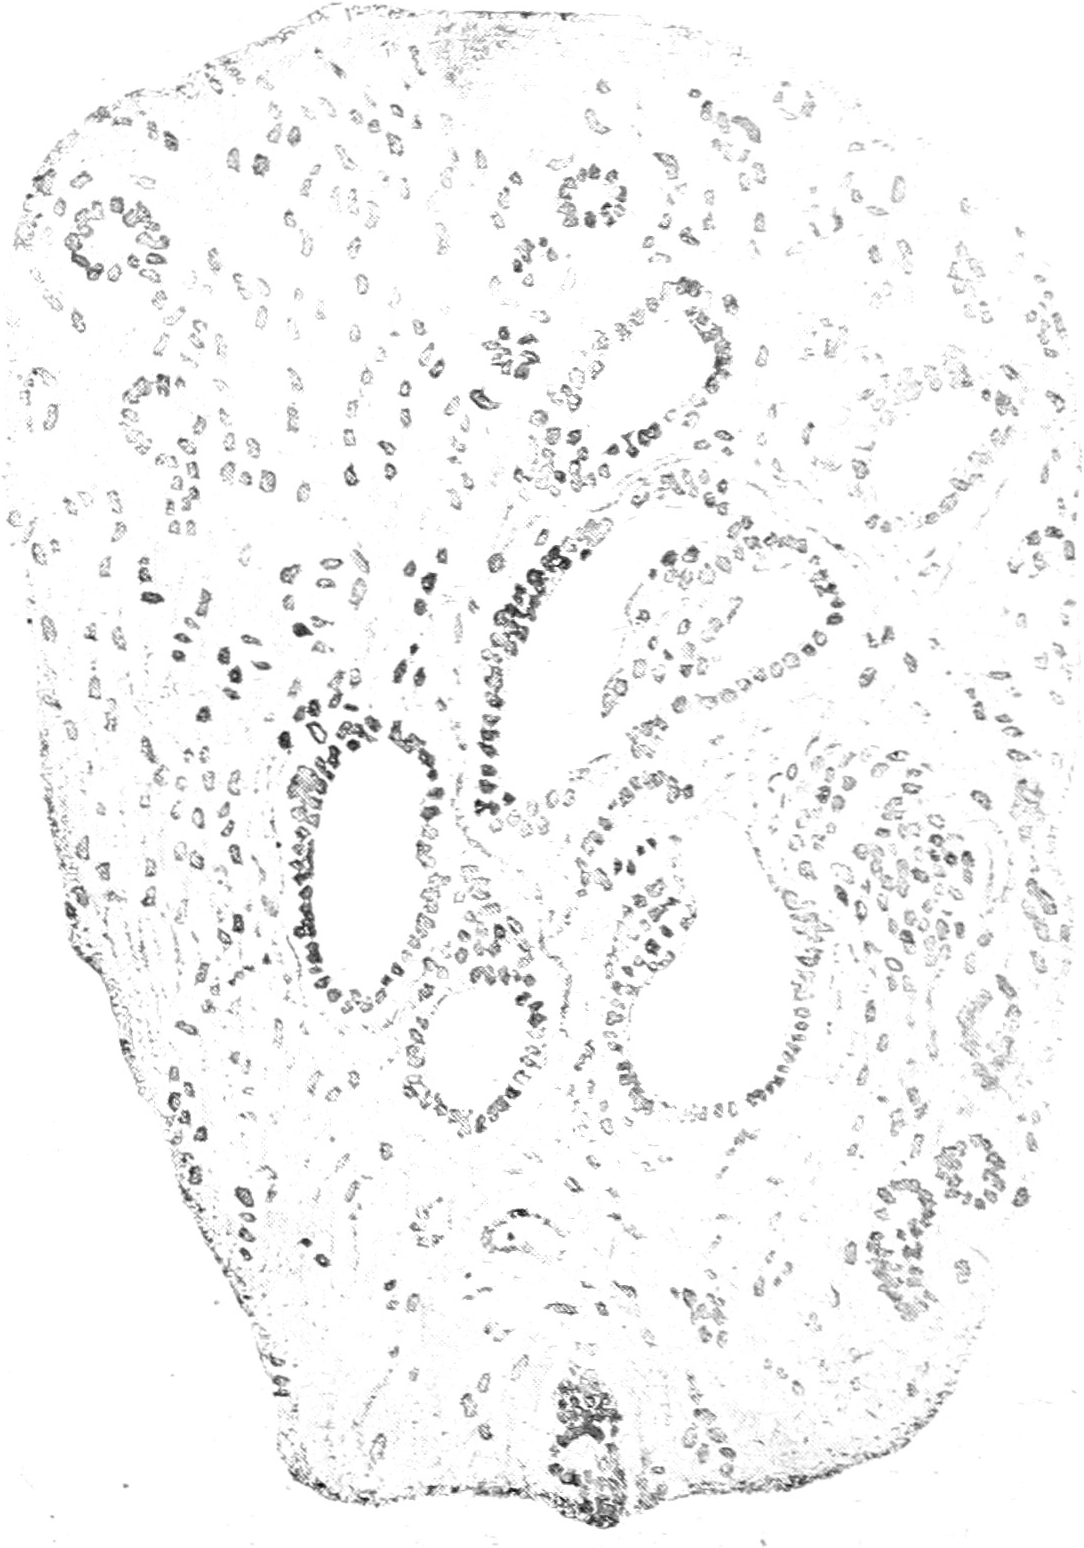

Рис. 1.

При микроскопическом исследовании печеночной ткани были обнаружены: жировая инфильтрация, застойная гиперэмия, участки с желчной пигментацией и очаговый некроз печеночных клеток. Жировая инфильтрация была резко выражена во всем органе. В области портальной системы повсюду замечалось неравномерное, очаговое развитие соединительной ткани, нигде, однако, не дававшей характерного для цирротического процесса в печени, окаймляющего сосуды и желчные протоки, разрощения. Вокруг фокусов начинавшегося разрощения ее встречалась сильно выраженная мелкоклеточная инфильтрация; в фокусах более старых круглые клетки инфильтрата отступали на задний план, и преобладали фибробласты, а с течением времени соединительная ткань принимала характер бедной ядрами волокнистой ткани, зачастую гиалинизированной. Соединительнотканные очаги сопровождались мощным разрощением эпителиальных ростков в виде трубчатых полостей (см. рисунок), которые, смотря по разрезу в продольном или поперечном направлении, имели различный вид: они были то вытянуты, в виде узких трубок, то представляли правильные кружочки, заложенные в соединительнотканной основе. Выстилавший их эпителий везде был однослойный цилиндрический с хорошо окрашивавшимися пузырчатыми ядрами и ничем не отличался от эпителия желчных ходов, почему мы можем с полным основанием сказать, что имели пред собой сильное разрощение последних. Желчные ходы, облитеруясь и постепенно увеличиваясь в об’еме, благодаря постоянному притоку секрета и повышенному давлению, превращались, очевидно, в об’емистые кисты Эпителий в последних был тот же цилиндрический, несколько лишь уплощенный, а местами—в больших образованиях—-кубический. Нередко на препаратах можно было наблюдать, как кисты, увеличиваясь и тесно прилегая друг к другу, теряют смежную соединительнотканную перегородку и превращаются в одну кисту несколько больших размеров. Эти большие кисты в свою очередь давали бухтообразные выпячивания, которые, отшнуровываясь, образовали дочерние кисты. Кисты почек были выстланы низким цилиндрическим эпителием и наполнены коллоидным содержимым. В яичниках микроскопически было обнаружено много мелких одиночных полостей с кубическим эпителием, местами переходившим в многослойный плоский.